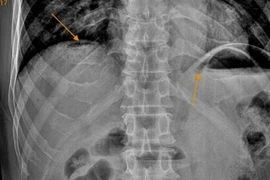

Người đàn ông 61 tuổi đến bệnh viện khám trong tình trạng đau bụng đột ngột dữ dội như dao đâm vùng thượng vị, sau đau lan khắp ổ bụng,... Các bác sĩ chẩn đoán bệnh nhân bị viêm phúc mạc do thủng tạng rỗng.

Người đàn ông đến bệnh viện khám trong tình trạng đau bụng đột ngột dữ dội như dao đâm vùng thượng vị, sau đau lan khắp ổ bụng,... Bệnh nhân được chẩn đoán viêm phúc mạc do thủng tạng rỗng.

Thủng tạng rỗng nếu không được chẩn đoán sớm và xử trí kịp thời sẽ biến chứng đe dọa tính mạng bệnh nhân, đây là tình trạng cấp cứu hết sức nguy hiểm vì ổ bụng bị nhiễm khuẩn do phân gây viêm phúc mạc toàn thể.